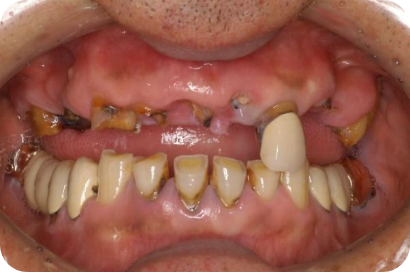

2025/12/10 / 最終更新日 : 2025/12/10 tom インプラント インプラント治療 – 複数本で安定した噛み心地を実現 インプラントを用いた治療例 複数のインプラントを使用し、固定式でしっかり咬めるようにする。 治療前後の比較 Before After 治療内容 インプラント治療 施術費用 通院回数 通院期間 メリット リスクと副作用